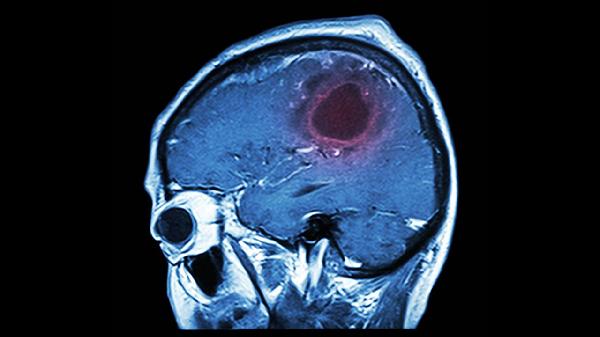

严重缺氧会导致意识障碍甚至昏迷,多见于急性肺栓塞或心脏骤停。需立即进行心肺复苏并急诊就医,必要时气管插管机械通气。恢复期可使用胞磷胆碱钠注射液促进苏醒,联合依达拉奉注射液清除氧自由基。